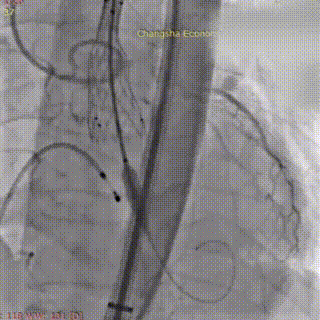

术中影像:

18mm球囊预扩

在调整血管活性药物至更稳定剂量、并做好所有应急准备后,再次进行球囊预扩张。此次扩张过程顺利,未再发生严重循环波动。造影证实球囊位置准确,无腰征,扩张过程顺利,无瓣周漏加重及冠脉阻塞征象。确定VenusA Deluxe DL 23 mm 自膨式经导管主动脉可回收瓣膜系统,经超硬导丝送瓣膜输送系统平稳通过股动脉、髂动脉及腹主动脉,无阻力送至主动脉瓣环位置。经多角度造影确认瓣膜支架标记点与主动脉瓣环、冠脉开口相对位置。最终,将瓣膜稳定释放并锚定于标准解剖位置。造影及TEE显示:人工瓣膜支架展开形态良好,无显著瓣周漏;主动脉瓣前向血流显著改善,平均压差大幅下降;左右冠状动脉显影清晰,患者血流动力学指标立时改善。